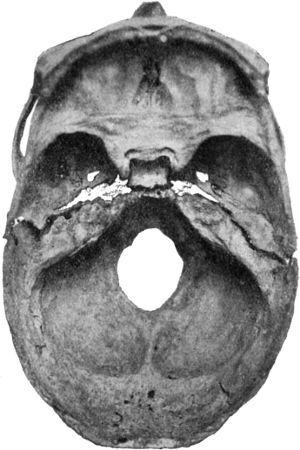

| 191. | Transverse Fracture through Middle Fossa of Base of Skull | 368 |

| 276. | Branchial Carcinoma | 601 |